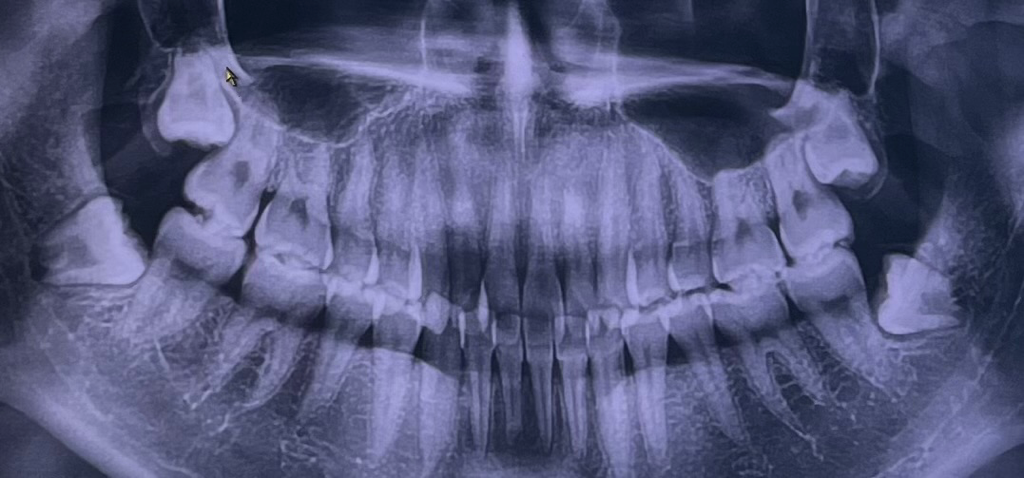

현재 교정중인데 사랑니가 누워있고 매복이라 4개 다 발치해야 한다고 합니다.(그동안 통증은 전혀 없었습니다.) 여기 사진 첨부해서 올리면 전문가분들이 뽑기 쉬워보인다 아니다 정도는 말씀해주시는 걸 보고 저도 올려봅니다.. 그리고 신경선?을 잘못 건드리면 마비가 온다는 얘도 있던데 저는 어떤가요.. 안전하게 뽑을 수 있을까요? ㅠㅠ 심지어 두달에 걸쳐 2개씩 뽑는다는데 원래 한번에 두개씩 뽑기도 하나요? ㅠㅠ 치과에선 "매복이라 안빠지면 치아를 깨서 뽑아야 할 수도 있다, 뽑는 힘 때문에 머리가 흔들릴 수도 있다" 이런식으로만 말씀하시니 무서워서 더는 묻질 못하겠더라구요. 답변 주시면 감사하겠습니다 ㅠㅠ

1.사랑니 뿌리가 신경관과 근접해 있기 때문에 감각이상이 올 수는 있지만 가능성은 낮습니다.

3.사랑니가 경사져 매복되어 앞의 어금니에 걸려 있으니 치아 부수는 치아절단술로 뽑아야 합니다.

신경손상 가능성은 낮아보입니다.

신경 근처에 깊게 매복 되어 있거나, 치아가 많이 누워있는 경우가 아닌 일반적인 매복 사랑니의 모습이므로 크게 걱정 안하셔도 괜찮습니다